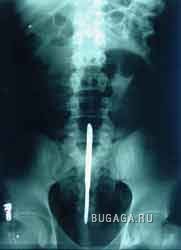

Ни для кого теперь уже не секрет, что у людей есть жопы. У каждого она своя и у всех разные. Жопы бывают человеческие и другие, большие и маленькие, плоские и выпуклые, висячие и упругие, в общем, всякие. А еще жопы бывают сытые и голодные. У кого сытая попа, тот её холит и лелеет, она вся такая ранимая и нежная. А у кого голодная жопа, тот её пичкает всем, что попадётся под руку, может затолкать туда всё, что угодно. Такую жопу ничто не берёт. Ни слово, ни дело, ни заноза, ни пуля, ни штык, ни добрый подсрачник! Прозвали их люди чудо-жопы! Чудо-жопы имеет не каждый, а только тот, кто регулярно упражняется в скармливании жопе различных инородных предметов. Этих ректальных сластолюбцев люди тоже кое-как прозвали, но мы не будем отвлекаться, с нас достаточно знать факт, что люди имеют жопы. Кто воспламенел желанием поэкспериментировать, но не знает, что именно засунуть в недра своего драгоценного проголодавшегося зверя, предлагаю посмотреть варианты. Ну а кому просто интересно, тот глазеет на серию снимков, сделанных медиками в разное время и в разных странах, но в одинаково патологичных случаях. Можно также прочитать пару случаев кормления, и чем это закончилось. Кого картинки могут задеть за живое, не принимайте близко к… живому :):):)

Список вещей, извлеченных из чудо-жоп:)

Разные предметы:

Железный прут -1